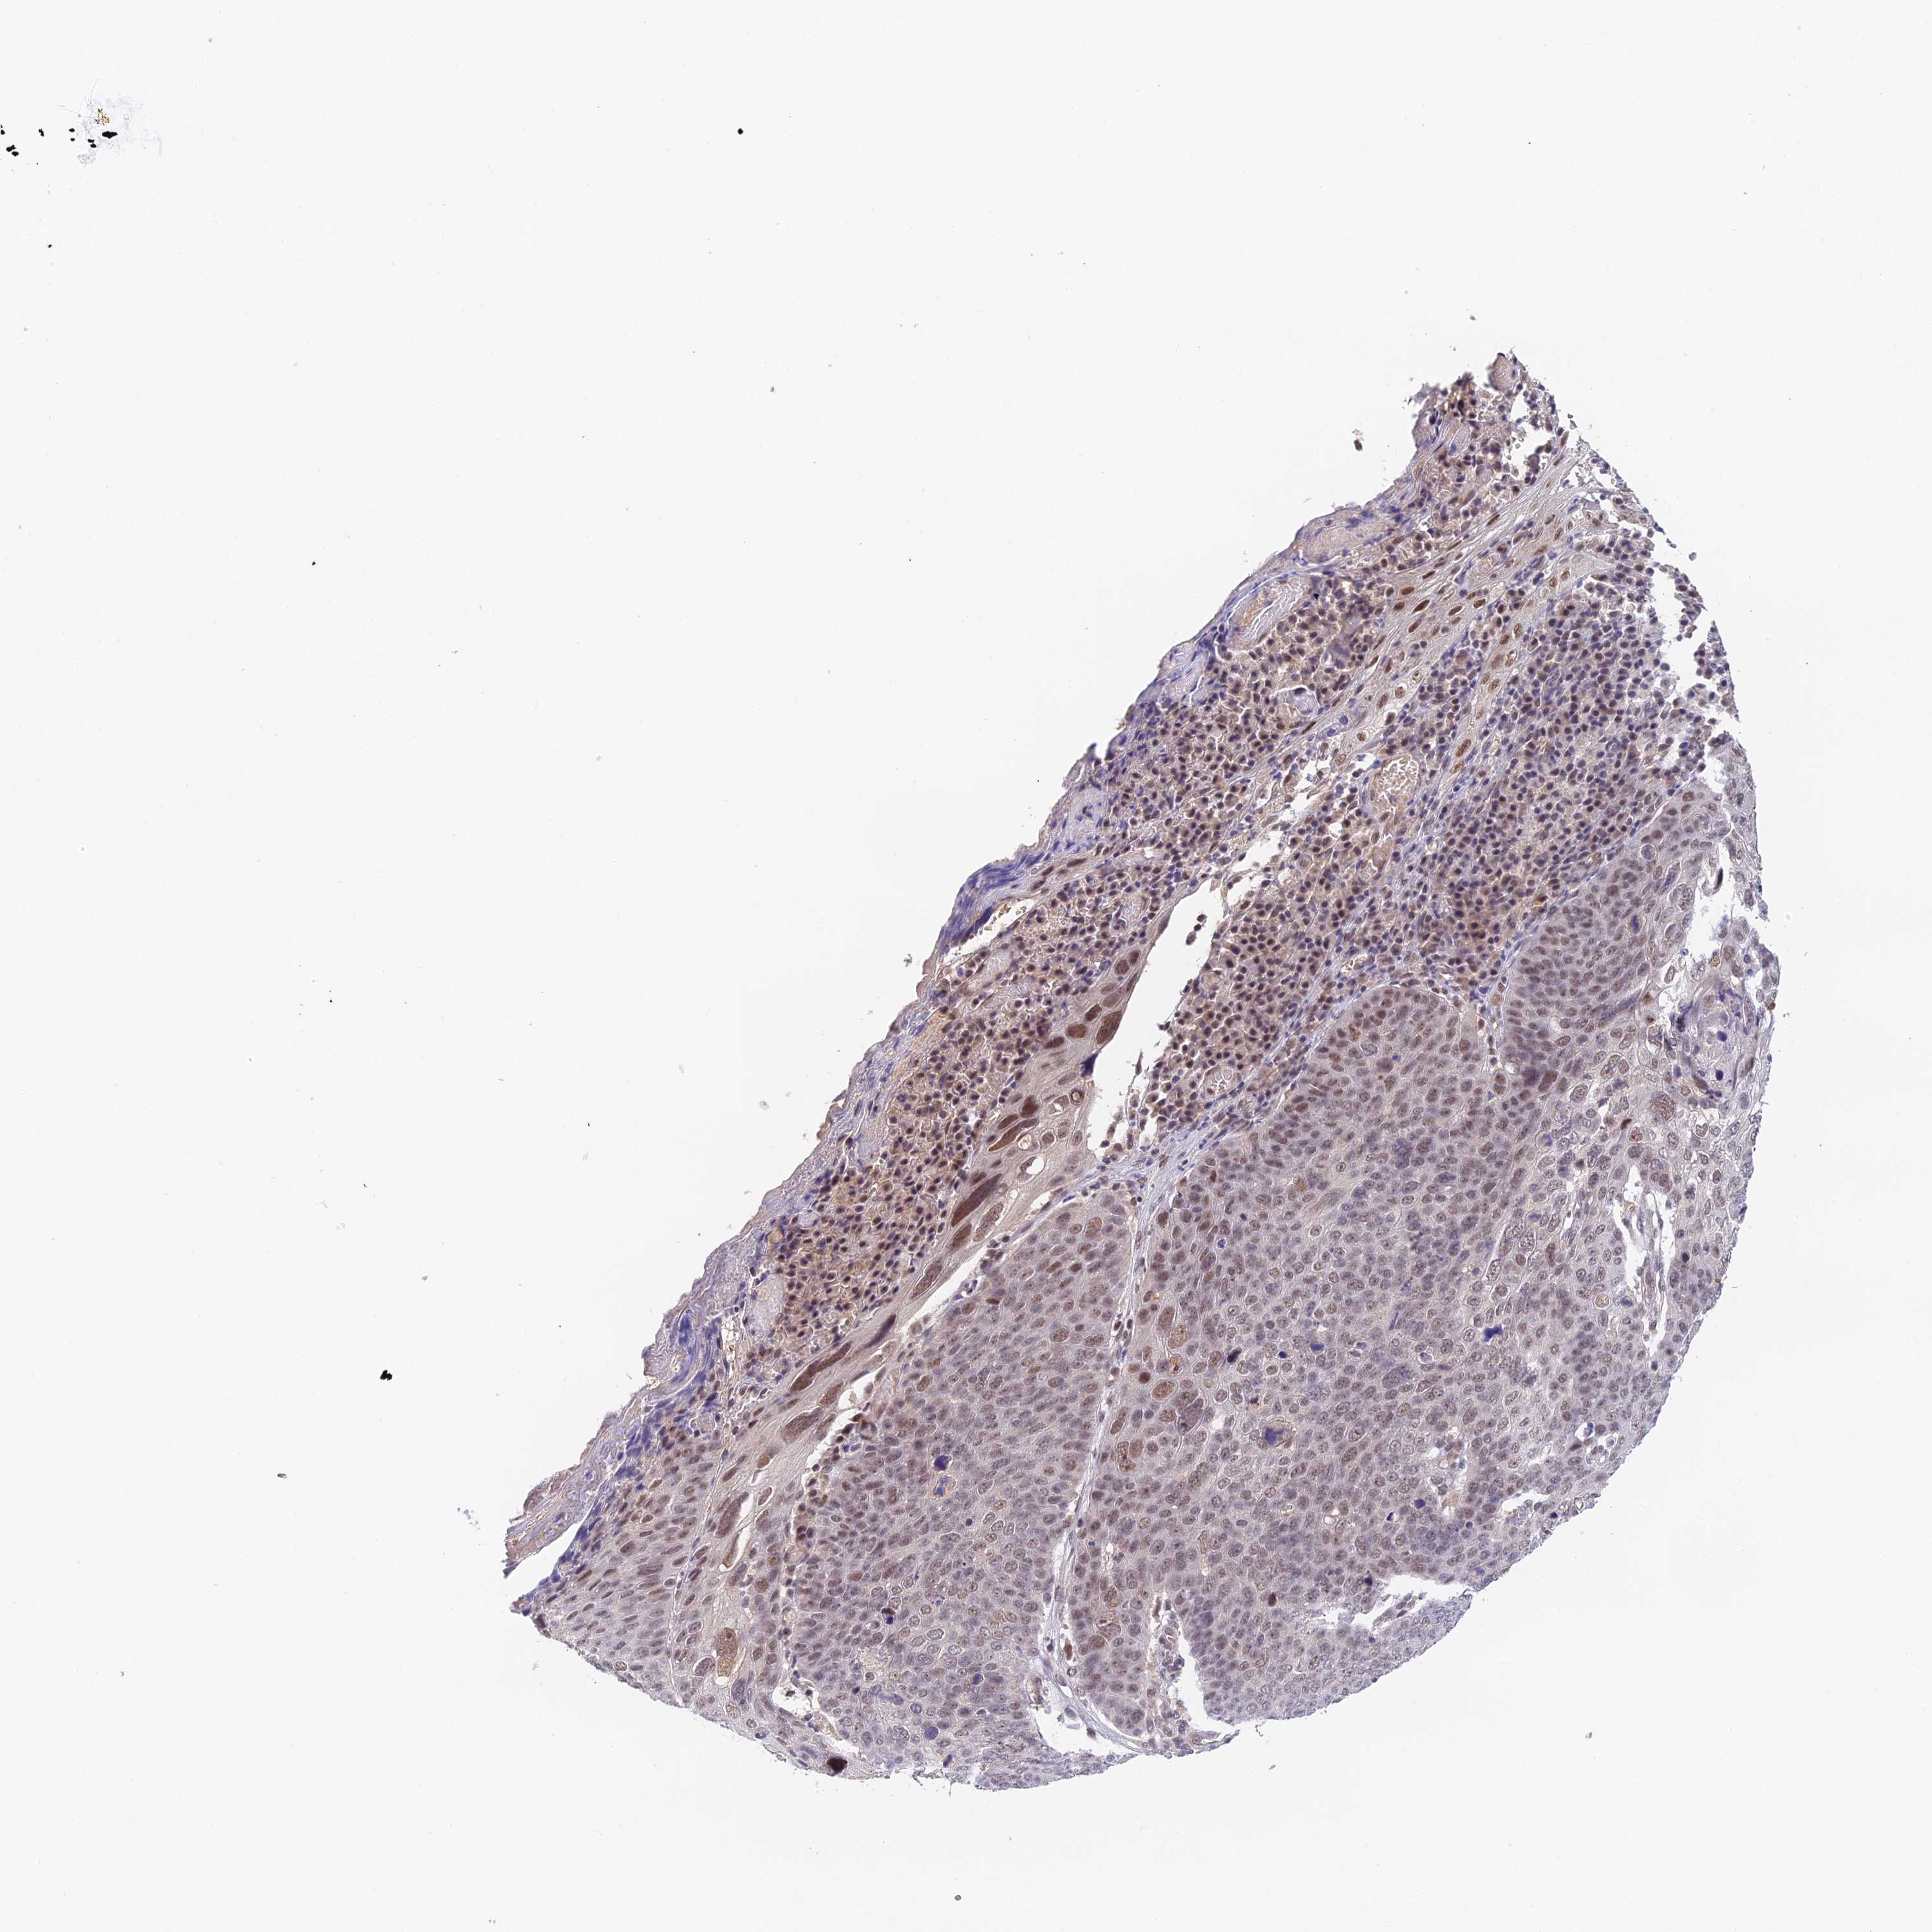

Basal cell and squamous cell cancer

SKIN CANCER - Protein expressioni

A mouse-over function shows sample information and annotation data. Click on an image to view it in a full screen mode. Samples can be filtered based on level of antibody staining by selecting one or several of the following categories: high, medium, low and not detected. The assay and annotation is described here.

Each image is clickable and will lead to virtual microscopy that enables deeper exploration of all samples and also displays staining intensity scores, fraction scores and subcellular localization as well as patient and tissue information for each sample.

Antibody HPA038395

Basal cell carcinoma